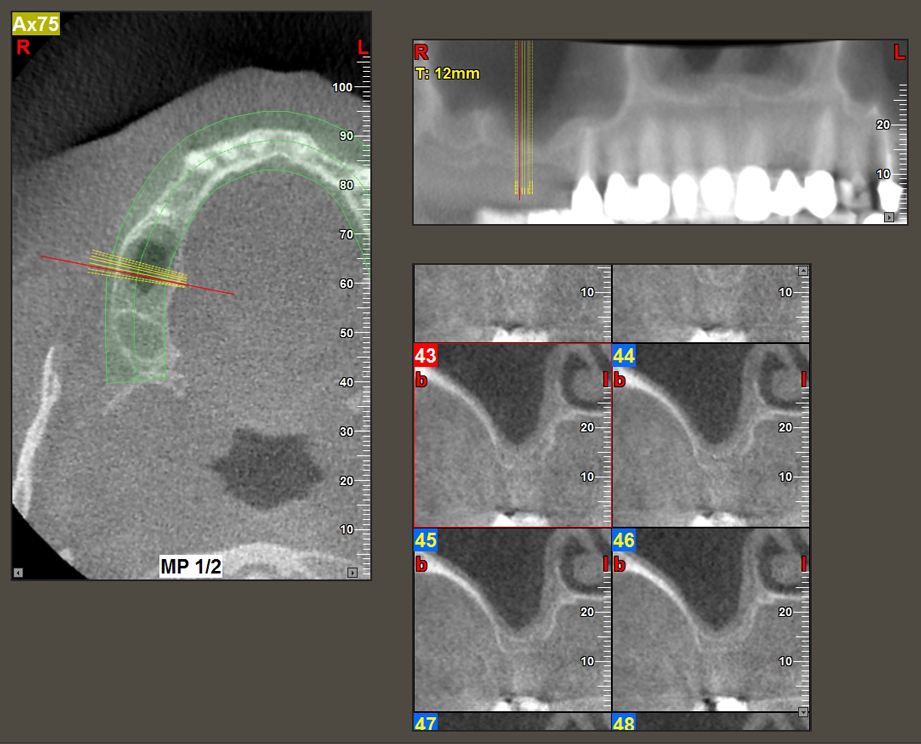

A 49-year-old female patient, a non-smoker and with nothing remarkable in her general medical history, was referred to our oral surgery practice for surgical extraction of tooth 16 and subsequent implantation. After the extraction, the patient experienced mild sinusitis trouble with the resultthat we initially waited six months before carrying out the measure. The residual bone height at the planned implant position measured 3-4 mm (Fig. 1 and 2).

The I2A instrument (diameter 2.0 mm) was then used to perforate the sinus floor intermittently and on the smallest scale possible. This special piezosurgical method ensures that the Schneiderian membrane is not damaged. When the Z25P was used, the membrane was already lifted slightly by the coolant supplied via the instrument tip (Fig. 3). The coolant quantity was just 50% in order to avoid high pressure in the implant bed.

Implant bed preparation and augmentation

Following an intermediate check (Fig. 4) a further preparation step was performed (Fig. 5). Afterwards, the hydraulic Z35P instrument was used to lift the membrane to the desired position (Fig. 6 and 7). This was followed by further piezosurgical preparation of the implant bed, concluded with a rotary bur and shoulder milling cutter up to the implant diameter of 4.8 mm. Before the implant was inserted, the augmentation material (particle size approx. 0.8-1.6 mm) was introduced underneath the Schneiderian membrane (Fig. 8).

To move the augmentation material in the direction of the maxillary sinus atraumatically, the implant was inserted very slowly by hand (Fig. 9). In the process, the membrane was pushed in the cranial direction once again. After two months, the surgical site healed without irritation. Six months later, the x-ray check showed a significant increase in opacity as an indication of ossification (Fig. 10). The prosthetic restoration was carried out with a metal-ceramic crown.